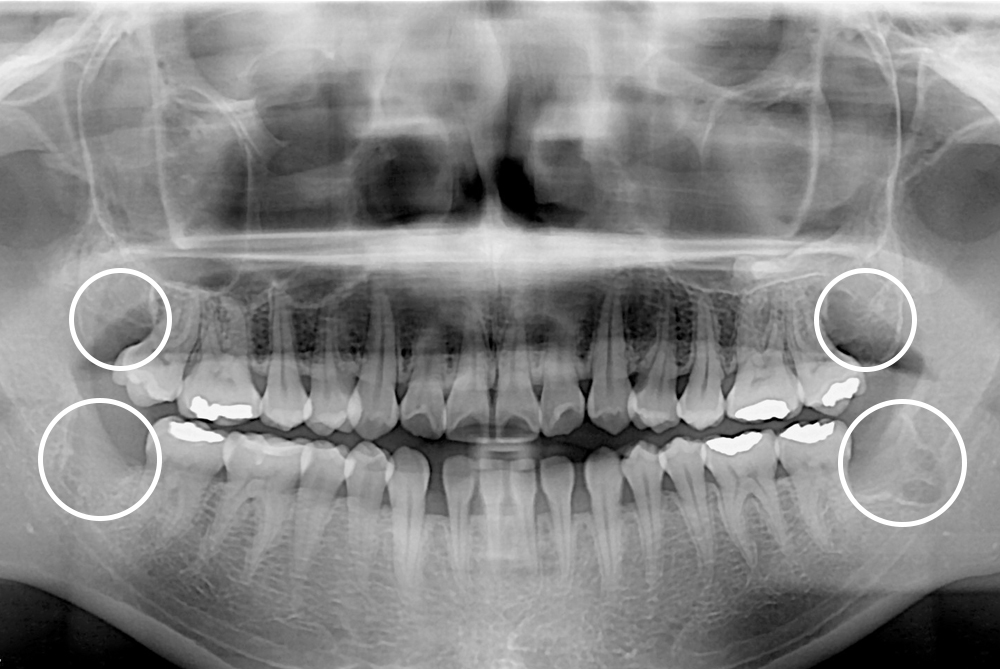

[사랑니] 매복 사랑니 발치

치료후 : 2019-07-06

세종치과는 구강악안면외과학 박사이신 원장님이 발치하는 치과입니다.